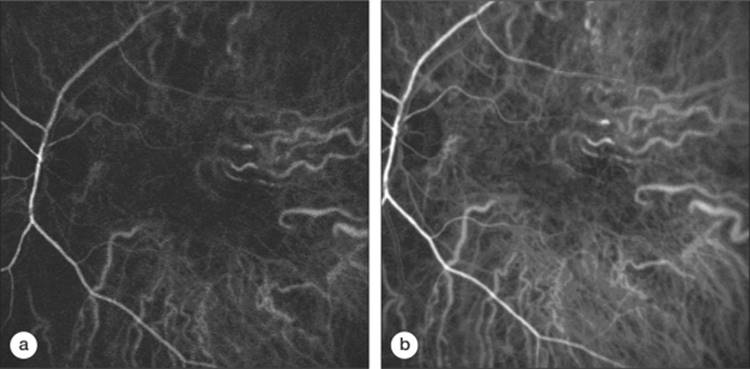

Four to six vortex veins receive the blood collected in the ampullae of the vortex veins by the afferent ones. The vortex veins are located 2.5-3 mm posterior to the equator, closer to the vertical meridian than to the horizontal one and drain into the superior and inferior orbital veins (Fig. 126.5).[46] Some drainage also occurs through the anterior ciliary veins of the ciliary body. Venous drainage sems to be segmentally organized into quadrants, with watersheds oriented horizontally through the disk and fovea and vertically through the papillomacular area (Fig. 126.6).[43,47]

Click to view full size figure

FIGURE 126.6 Indocyanine green angiogram of early (a) and late (b) choroidal arteriovenous phase. Note the subfoveal entry of short posterior macular arteries, the vertical arterial watershed area running through the papilla, and the venous watersheds oriented horizontally though the disk and fovea and vertically through the papillomacular region.